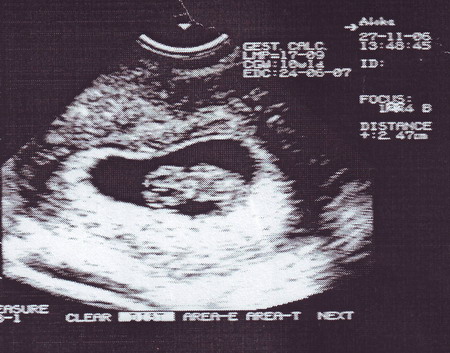

) в возрасте 9 недель. Вот так он выглядел при нашем с ним первом знакомстве.

Нам поставили срок "уверенные девять недель" и написали в результатах УЗИ "прогрессисующая маточная беременность"